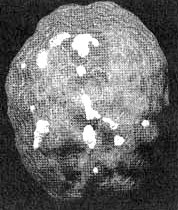

Мозг Линды. Результаты сканирования SPECT

Трехмерное изображение — активный мозг, вид сбоку.

До лечения: обратите внимание на выраженное усиление активности в поясной системе, в базальных ганглиях и в лимбической системе.